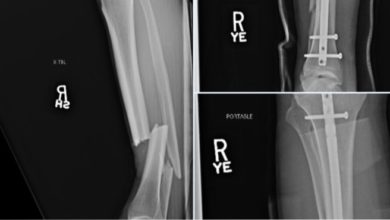

Chris Weidman partage une radiographie d’une jambe cassée

Chris Weidman partage une radiographie d’une jambe cassée L’ancien champion des poids moyens de l’UFC Chris Weidman s’est brisé la…